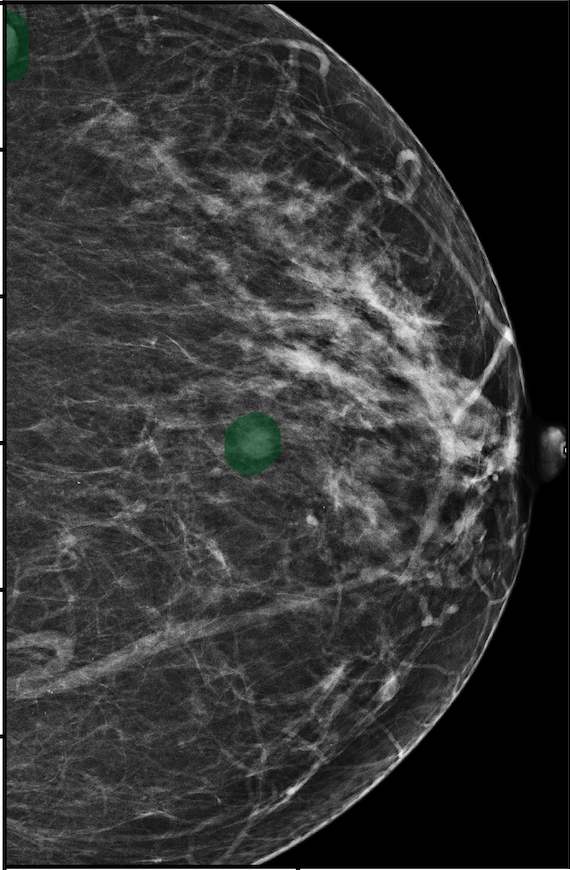

To better understand our model’s behavior, we visualize SMs of three samples selected from the test set in Figure 4. In the first two examples, the SMs are highly activated on the true lesions, suggesting that our model is able to detect suspicious lesions without pixel-level supervision. Moreover, the attention is highly concentrated on ROI patches that overlap with the annotated lesions. In the third example, the malignant SM only highlights parts of a large malignant lesion. This behavior is related to the design of : a fixed pooling threshold cannot be optimal for all sizes of ROI. Furthermore, this observation also illustrates that while human experts are asked to annotate the entire lesion, CNNs tend to emphasize only the most informative part.